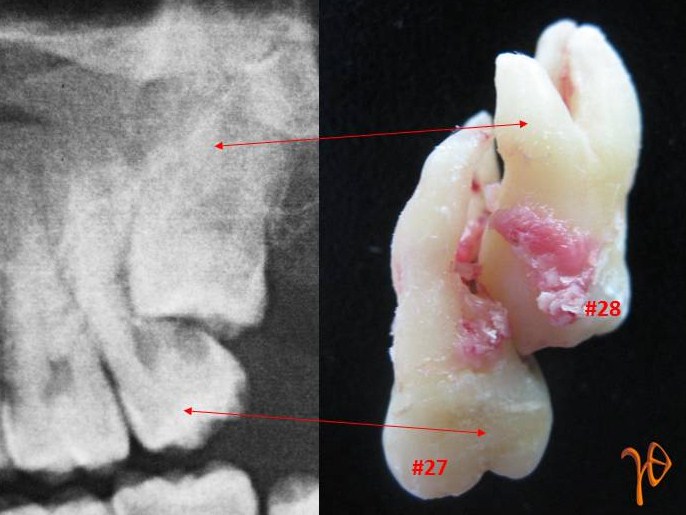

Εικονογράφηση μιας γνωστής ένδειξης για την χειρουργική αφαίρεση των φρονιμιτών.

(Resorption and caries of the roots of a maxillary second molar caused by the unerupted third molar).

Απορρόφηση ριζών άνω δεύτερου γομφίου λόγω εγκλείστου φρονιμίτη